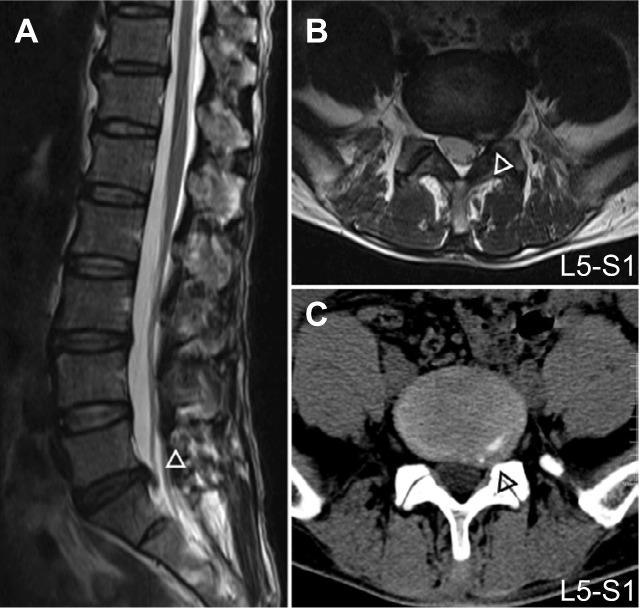

We obtained and compared the LFO amplitude from 25 right-handed discogenic LBLP patients (13 males; mean age 55.16±1.83 years) and 27 well-matched healthy controls (15 males; mean age 52.96±1.63 years). The LFO amplitude was examined using the voxel-wise amplitude of low-frequency fluctuations (ALFFs), and partial correlation analysis was performed to determine the relationship between the regions with altered ALFF values and clinical parameters in discogenic LBLP patients.